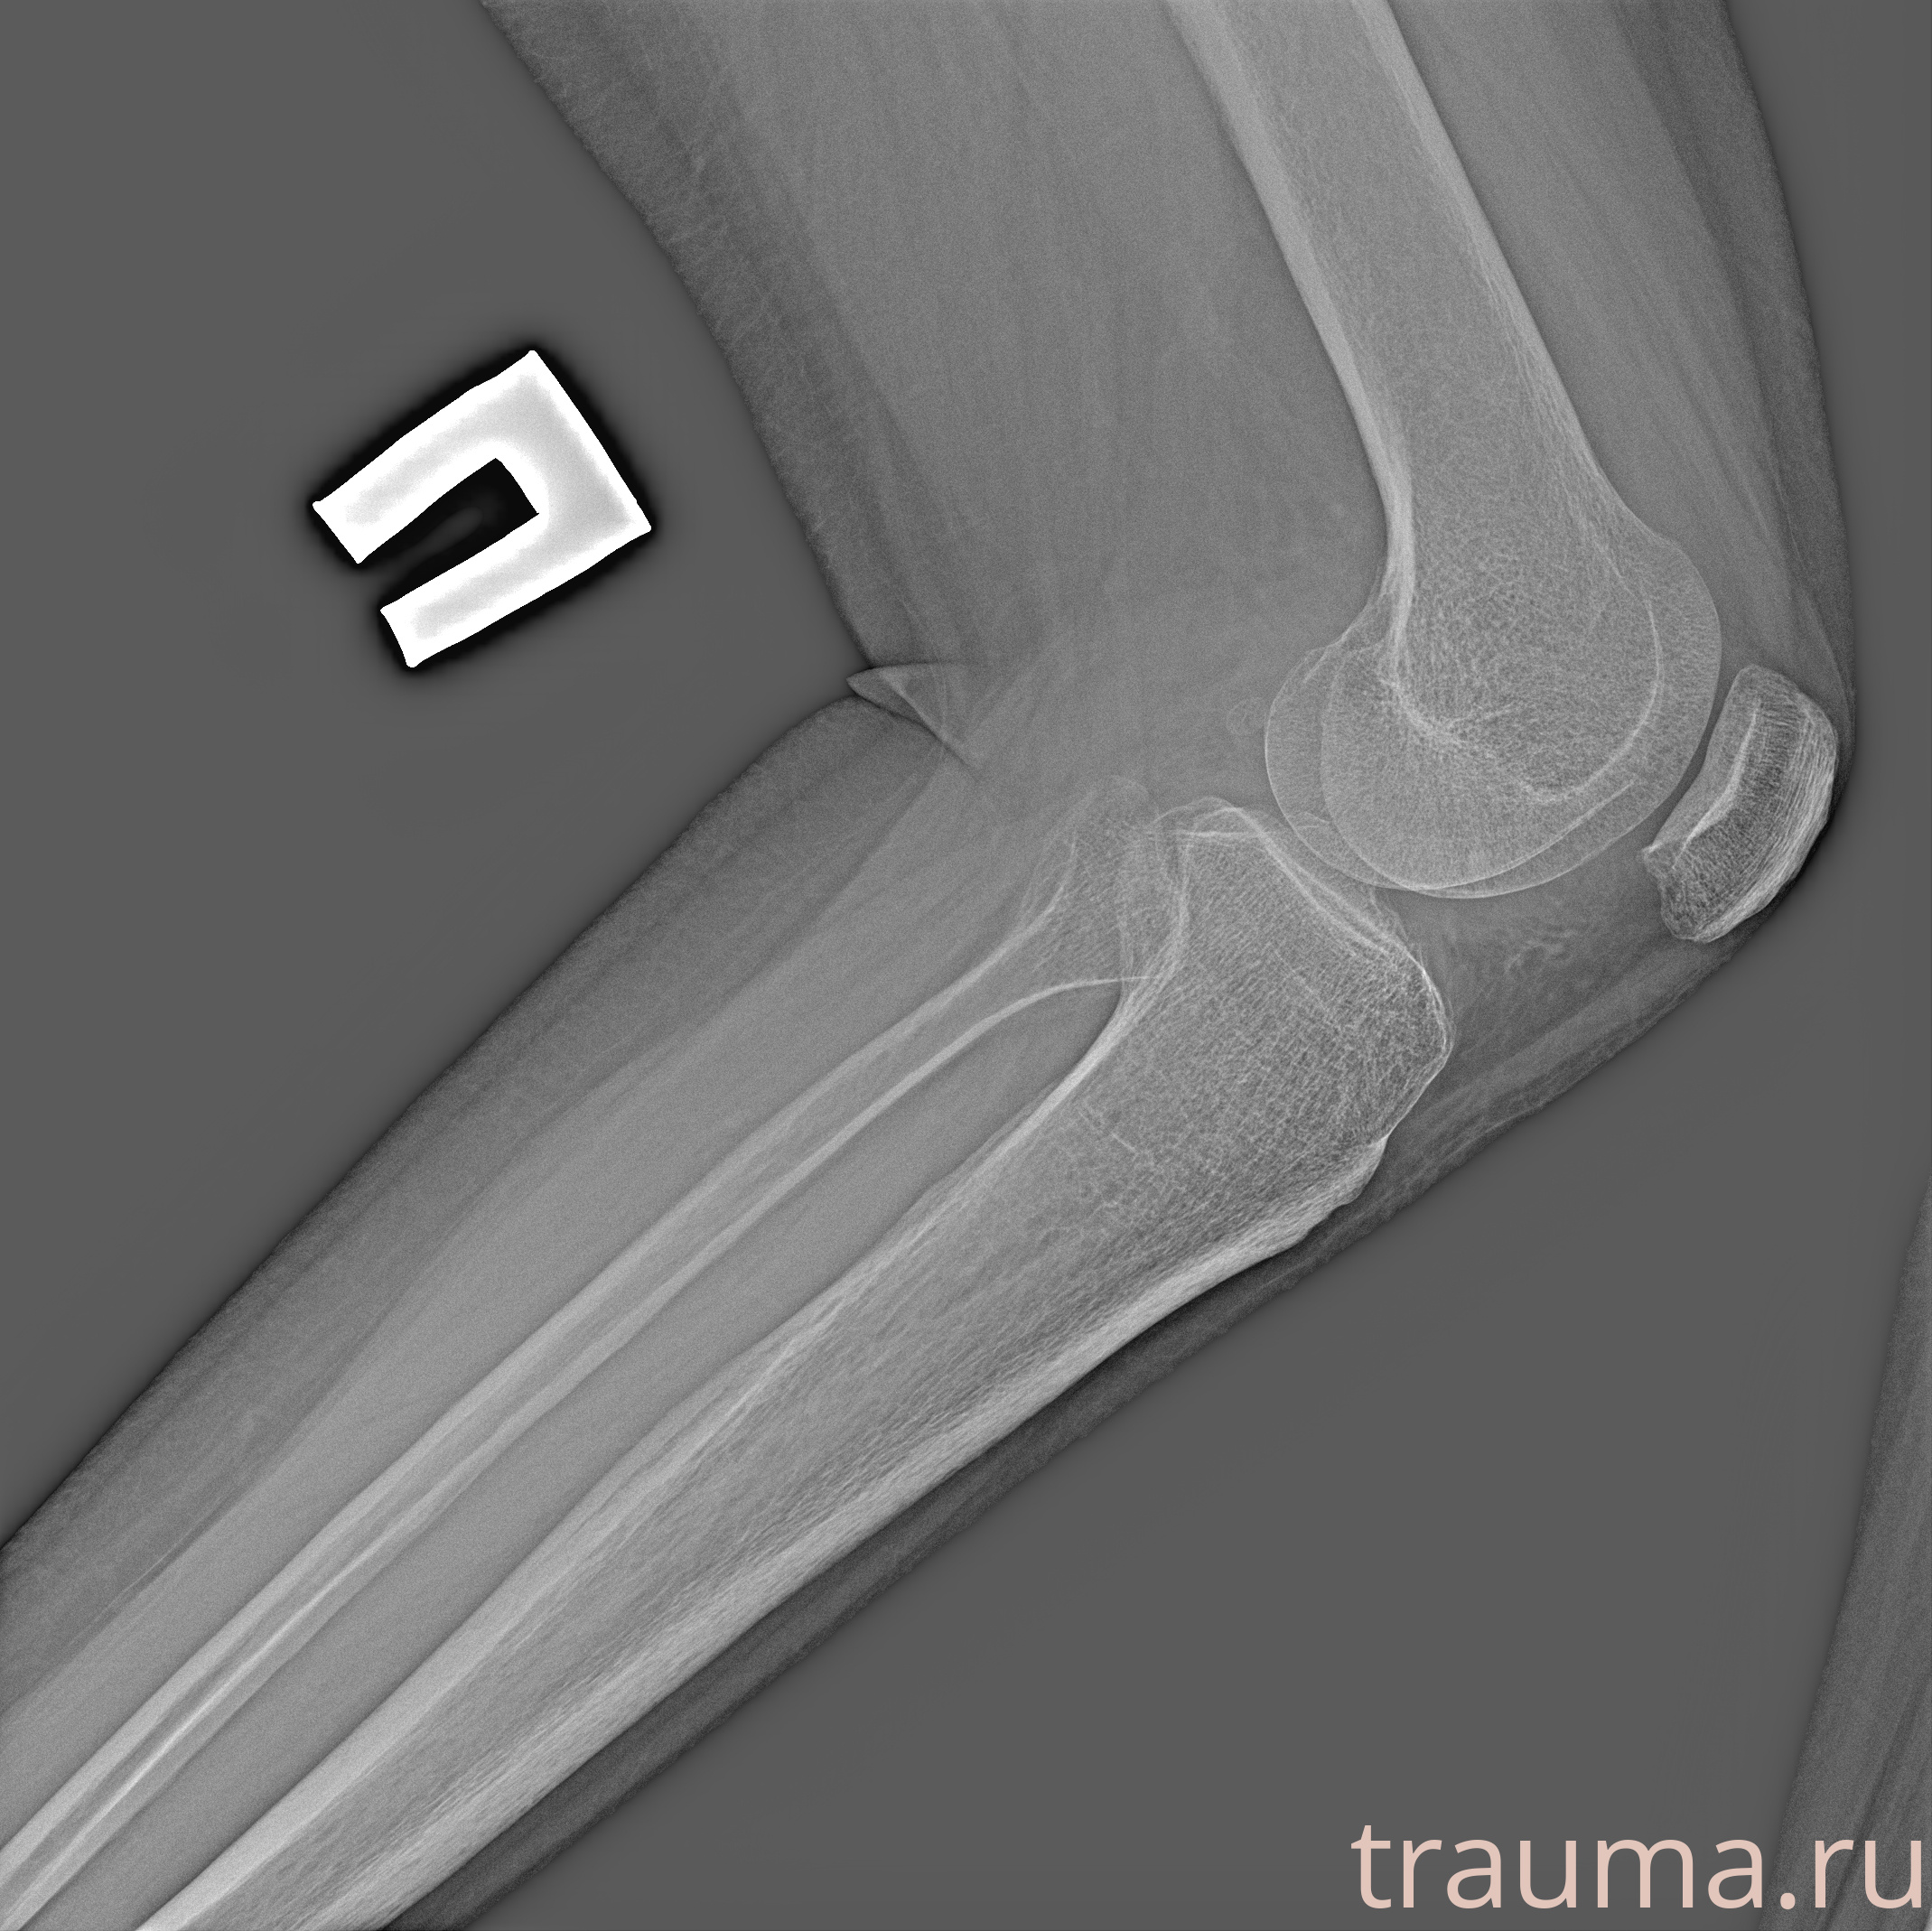

Рентгенограммы

Рентген на дому: по вашему адресу приезжает врач-рентгенолог, травматолог-ортопед с мобильным рентгеновским аппаратом, проводит диагностику травмы или заболевания, делает необходимые рентгенограммы, дает рекомендации по дальнейшему лечению. Получить качественные снимки в домашних условиях возможно благодаря уникальной методике, разработанной МосРентген Центром для института  Склифосовского